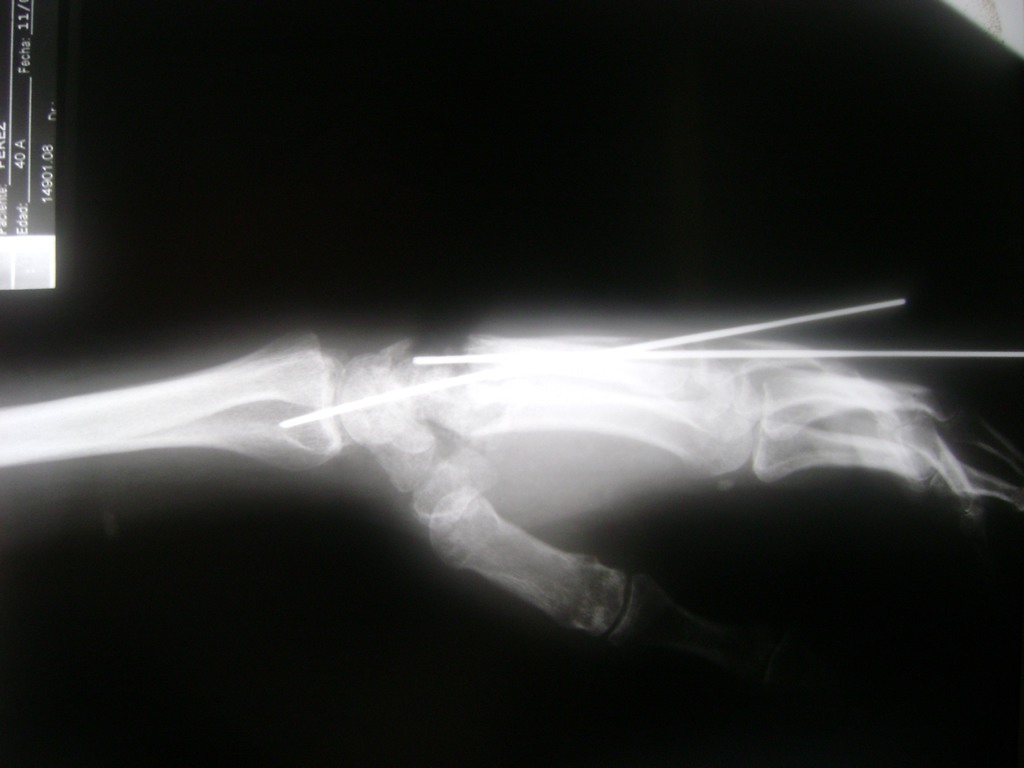

Cirugía de Fémur - Cirugías de Muñecas y Manos

Los procedimientos más comunes en cirugía de la mano son aquellos destinados a reparar traumatismos, incluyendo lesiones de tendones, nervios, vasos sanguíneos, y articulaciones; huesos fracturados; y quemaduras, cortes, y otros daños de la piel.